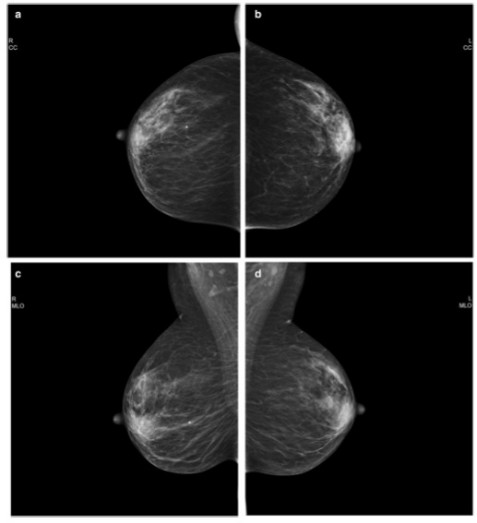

圖 使用PGMI系統(tǒng)歸類為 "完美 "的乳腺鉬靶照片。 a 以病人協(xié)助的壓縮模式獲得的右CC視圖。b 以標準壓縮模式獲得的左CC視圖。c 以病人協(xié)助的壓縮模式獲得的右MLO視圖

本項前瞻性隨機對照試驗在2017年9月-2019年12月期間進行。參與者是50至69歲的無癥狀女性,每位參與者均參加了第二輪或后續(xù)的乳腺鉬靶檢查。通過隨機分配,一個乳腺接受SC檢查,另一個乳腺接受PAC檢查。根據(jù)顱底(CC)視圖的10個標準和縱側斜(MLO)視圖的8個標準,圖像質量被評估為完美、良好、中等或不足(PGMI)。進行皮爾遜卡方檢驗,如有必要則進行Yates校正,以比較不同壓縮模式的圖像質量。

共有444名參與者被納入其中(平均[±標準差]年齡,60[±4.9]歲)。在CC視圖中,PAC和SC模式的PGMI百分比沒有差異(完美,37% [162/444] vs 37% [163/444];良好,1% [5/444] vs 2% [9/444];中等,62% [277/444] vs 61% [271/444];不足,0% vs 0. 2% [1/444]; p = .88)或MLO視圖(完美,53% [237/444] vs 56% [247/444]; 良好,22% [99/444] vs 22% [97/444]; 中等,23% [102/444] vs 22% [98/444]; 不夠,1% [6/444] vs 0.5% [2/444]; p = .72)。當按橫向分層或按PGMI標準分析時,也沒有發(fā)現(xiàn)統(tǒng)計學差異。